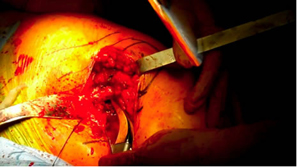

| Slightly more neck was removed |

Slightly more neck resection |

Some fine tuning with a high speed burr was done since we were on cortical bone.

This is not necessary but was helpful in getting a more custom fit |